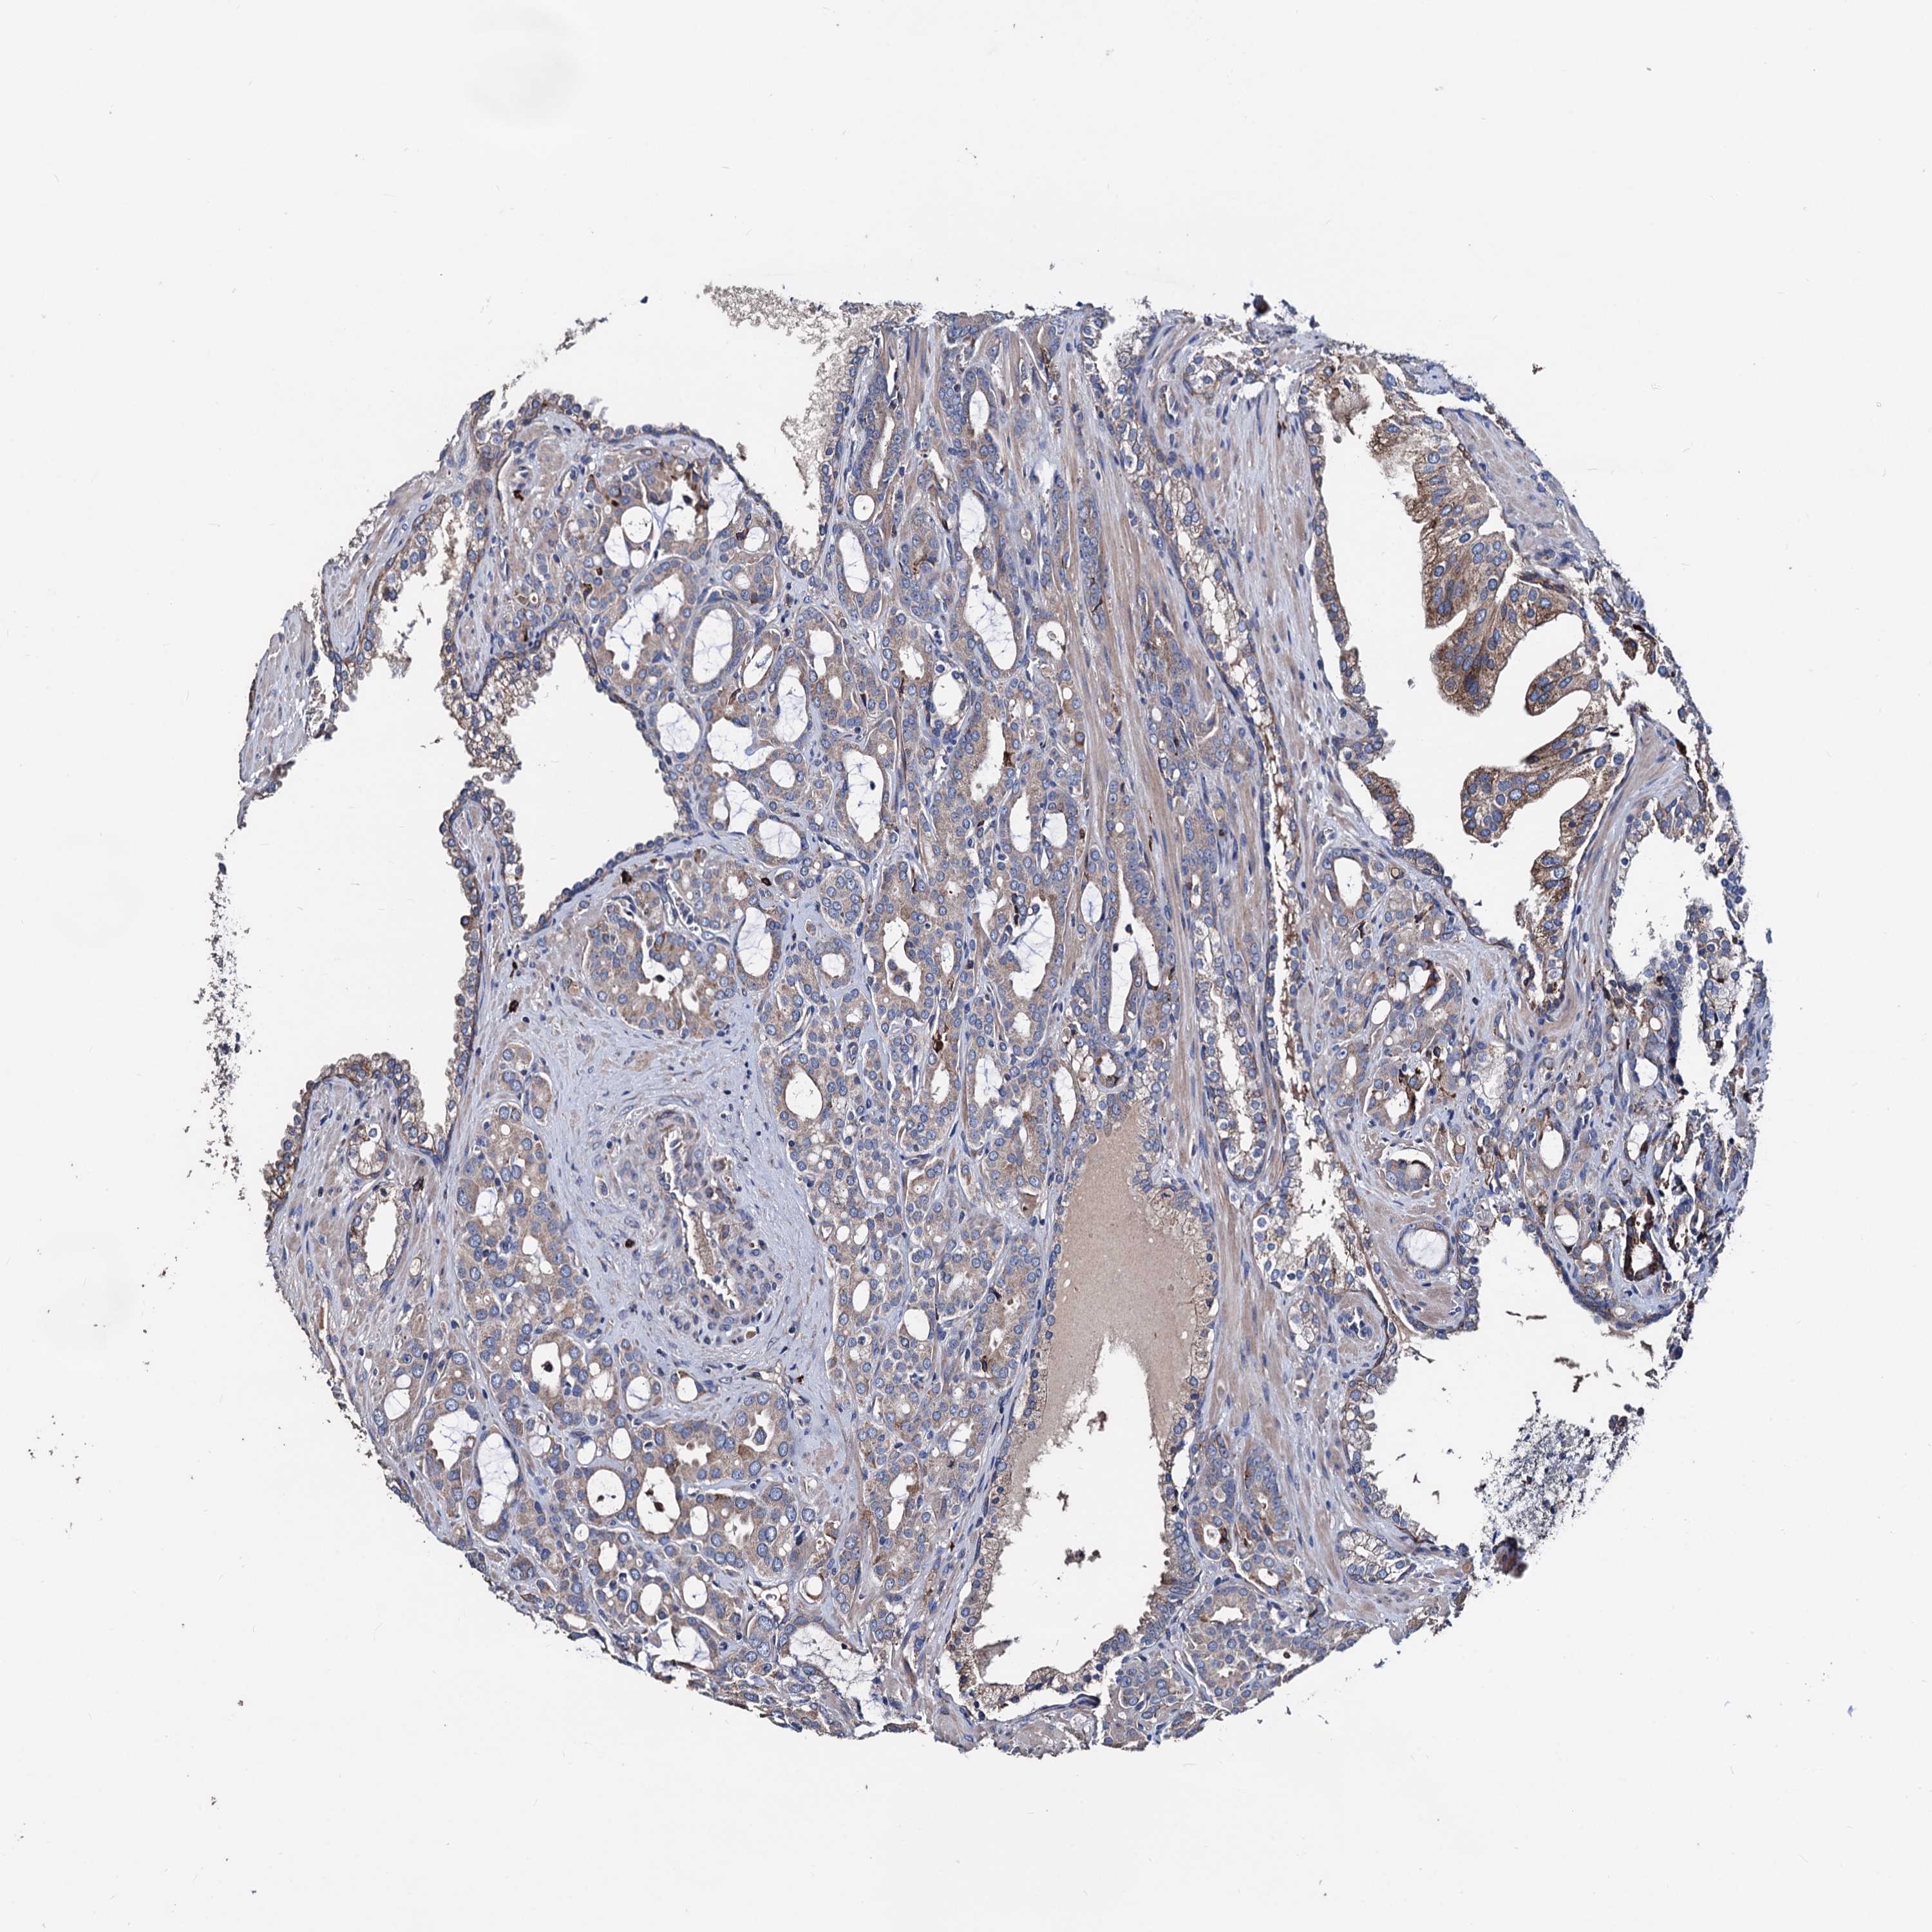

PROSTATE CANCER - Protein expressioni

A mouse-over function shows sample information and annotation data. Click on an image to view it in a full screen mode. Samples can be filtered based on level of antibody staining by selecting one or several of the following categories: high, medium, low and not detected. The assay and annotation is described here.

Antibody stainingi

Antibody staining in the annotated cell types in the current human tissue is reported as not detected, low, medium, or high, based on conventional immunohistochemistry profiling in selected tissues. This score is based on the combination of the staining intensity and fraction of stained cells.

Each image is clickable and will lead to virtual microscopy that enables deeper exploration of all samples and also displays staining intensity scores, fraction scores and subcellular localization as well as patient and tissue information for each sample.

Antibody HPA039089

Staining

High

Medium

Low

Not detected

Intensity

Strong

Moderate

Weak

Negative

Quantity

>75%

75%-25%

<25%

None

Location

Nuclear

Cytoplasmic/membranous

Cytoplasmic/membranous,nuclear

Adenocarcinoma, NOS

Adenocarcinoma, High grade

Adenocarcinoma, Low grade